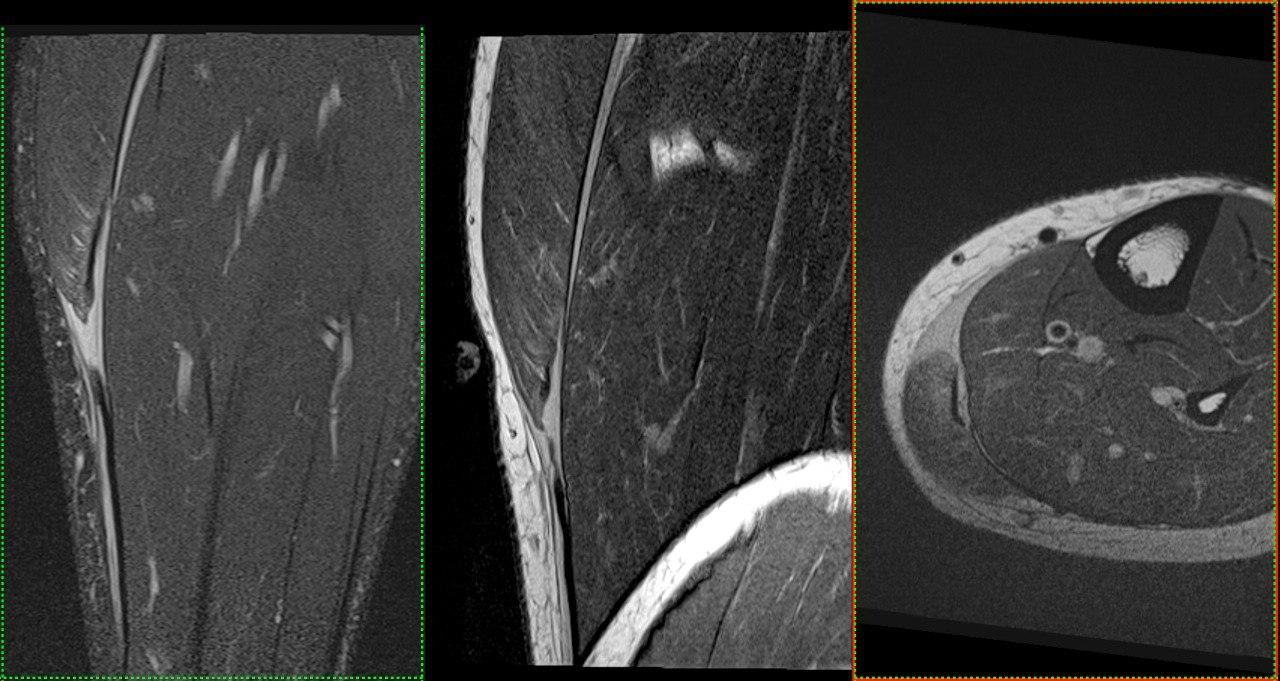

- МРТ: Створює найчіткіші зображення м’яких тканин, органів та судин. Без використання шкідливого випромінювання, тому також підходить для візуалізації вагітних, дослідженні плоду.

У нас є можливість проведення досліджень високої роздільної здатності всіх органів та систем (за винятком серця), зокрема в складі синдромів/комбінованих вадах. Обстеження виконуються, як для дітей так і дорослих пацієнтів, в т.ч. з анестезіологічним забезпеченням (седація, наркоз).

Магнітно-резонансна томографія: Найточніший метод для дослідження мозку, хребта, суглобів та м’яких тканин. Абсолютно безпечний тому також підходить для візуалізації вагітних, дослідженні плоду. Разом КТ та МРТ показані для виявлення вроджених аномалій розвитку/патології центральної нервової, скелетно-м’язової, травної, дихальної, сечовидільної системи, статевої сфери Також показані пацієнтам та потенційним донорам при підготовці до трансплантації,